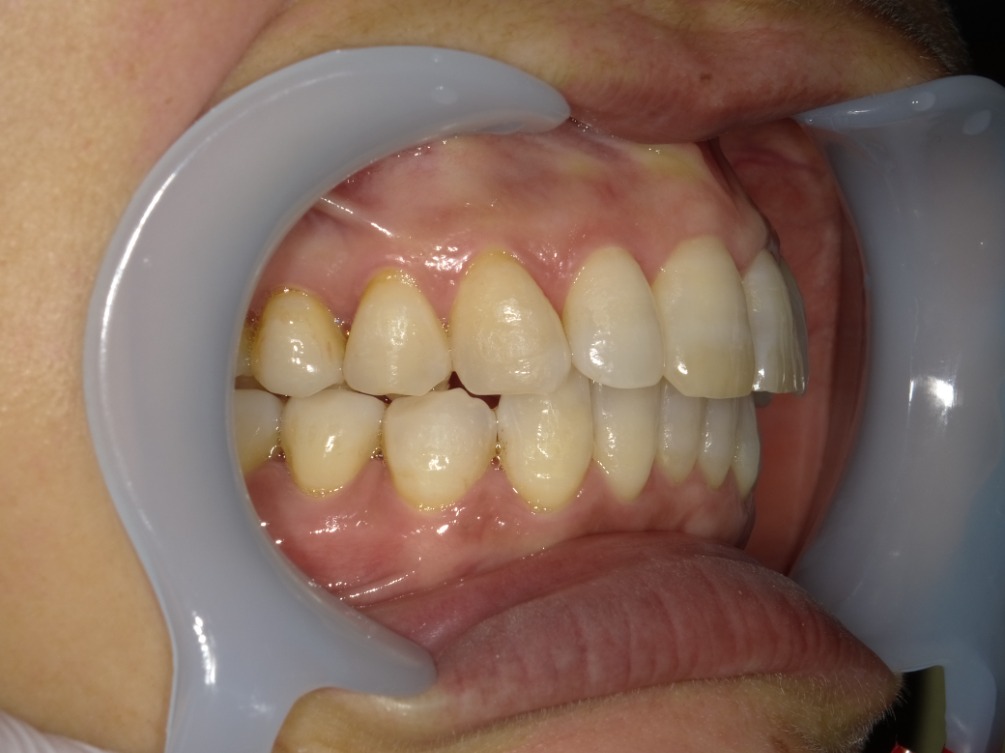

AFTER

右横